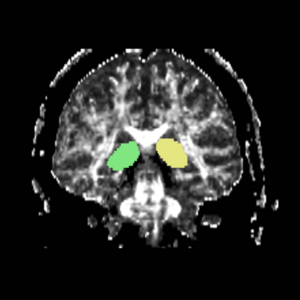

The most prominant (central) slice of the fornix was identified using a sagittal view (Fig. 5), and the ROI1s and ROI2s were drawn on the coronal slice adjacent to the most anterior point of the fornix (Fig. 6).

Figure 5. Sagittal view of the fornix, located centrally in the brain

Figure 6. Coronal View of ROI 1 and ROI 2, (left and right)

The color coding of the resulting ROIs is as follows:

ROI 1: Left(7) - Right(8)

ROI 2: Left(11) - Right(12)